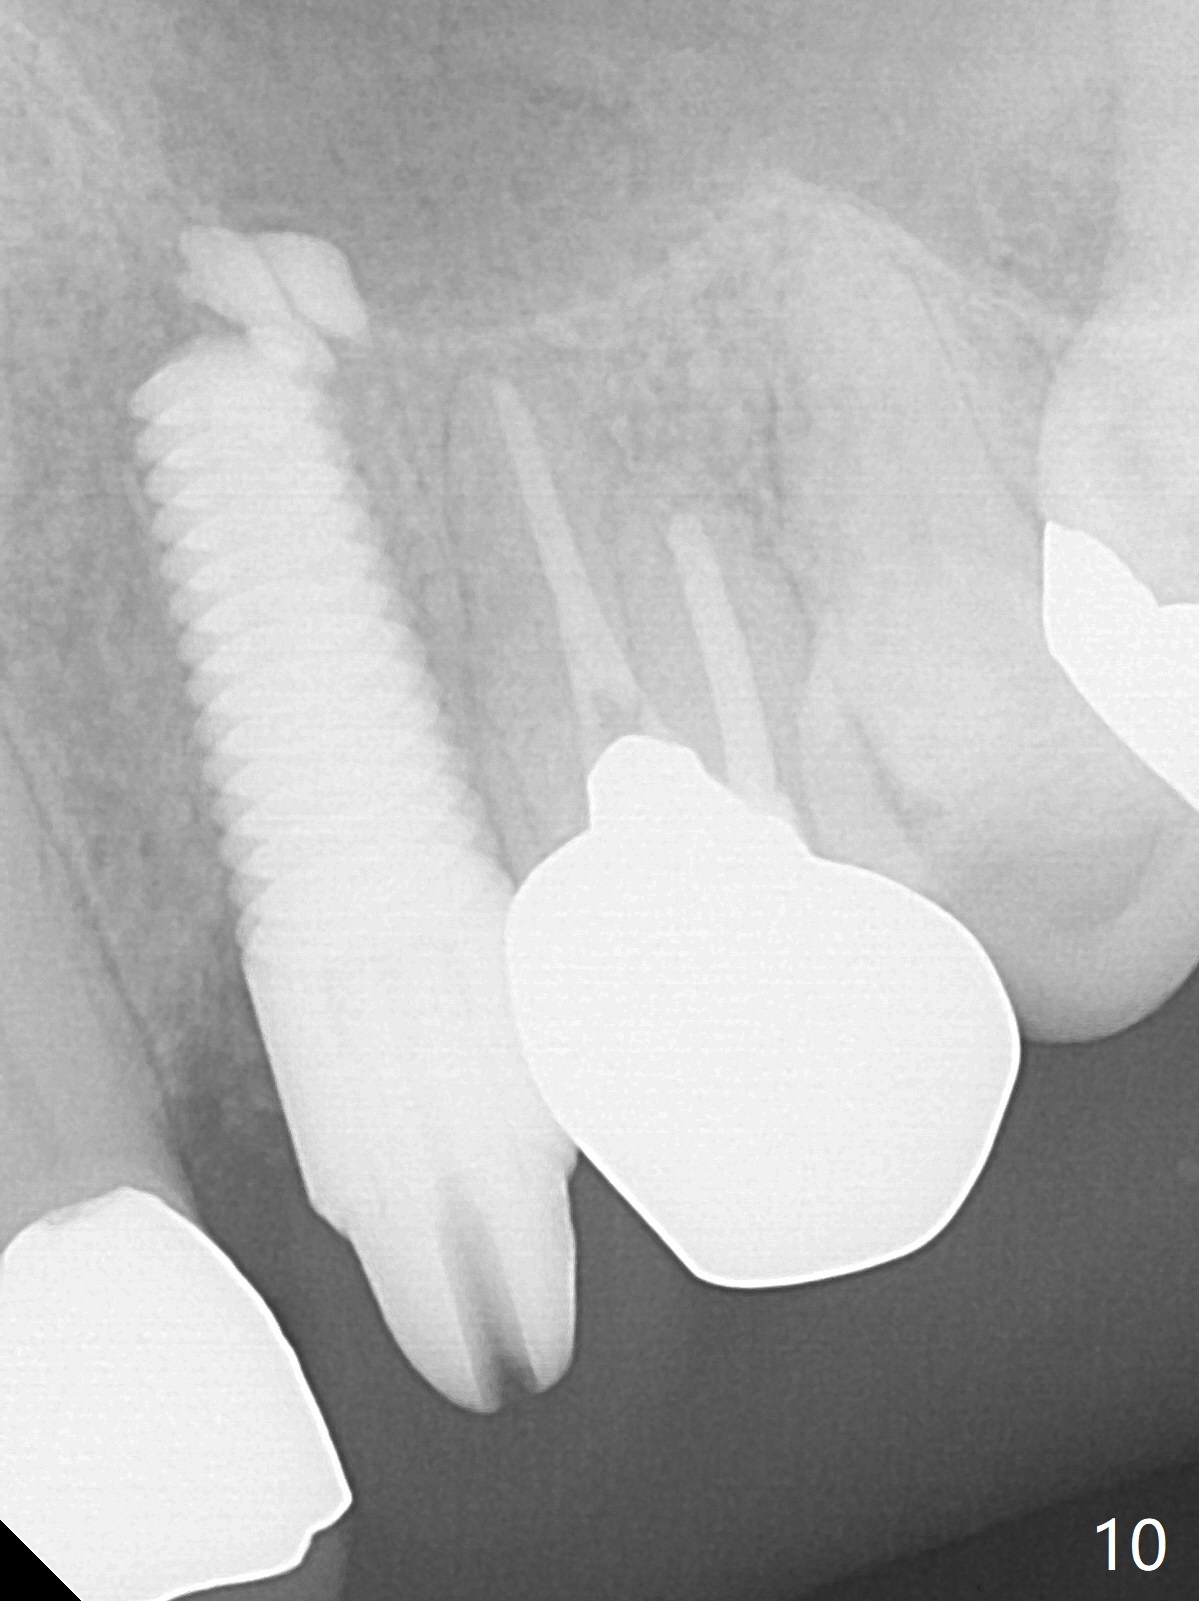

Extraction of the residual root at #11 (Fig.1) turns out to be difficult (Fig.2 (arrow: after use of small elevator). The tooth is sectioned (Fig.2 *); the palatal portion is removed, while the buccal one is trimmed until new moon-shaped and subgingival (Fig.3 * (gauze (G) packed in the socket while photo taking)). Initial osteotomy is 20 mm deep with nasal floor perforation (Fig.4). The subsequent depth is 17 mm (Fig.5). When a 5x17 mm tissue-level implant is placed (Fig.6,7; >60 Ncm), there is a gap between it and the socket shield (Fig.6 *). Gap-filling Vera Graft (Fig.8 *) also covers the shield prior to fabrication of an immediate provisional (Fig.9). There is no apparent bone loss 3.5 months postop (Fig.10). There is no buccal plate resorption 9 months postop (Fig.11). The implant is doing well 2 years postop (1 year 9 months post cementation, Fig.12).